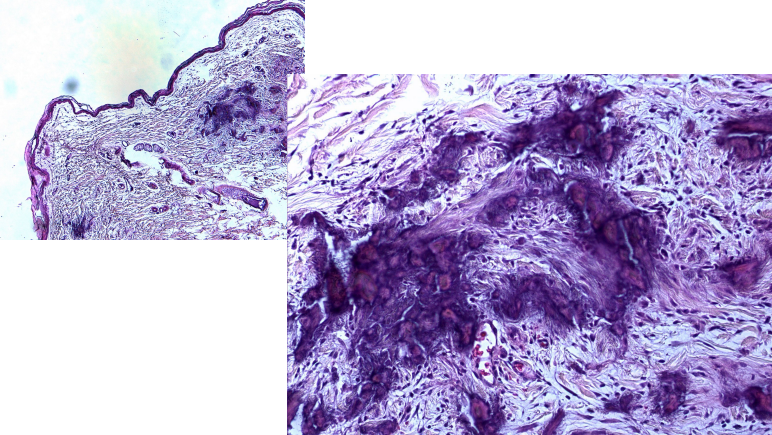

- Cytology : ํผ๋ถ (๊ฐ ์ธต์ ์ธํฌ๋ฅผ ํ๋ฝ์์ผ์ ๊ฒ์ฌ)

- dermal biopsy ํ์น ์ด์ฉํด์ punch biopsy (์ ์๊ณผ ๋น์ ์์ ๊ฒฝ๊ณ ๋ถ๋ถ) ; ์ง๊ฒฝ์ด ๋ ํผ (์ต๋ 1cm ์ ๋)

- hair follicle, sebaceous gland ๋ฑ ์๋ฌด๊ฒ๋ ๋ณด์ด์ง ์์.

- ๋ถ์ ํ์ ๊ฒฐ์ ์ด ์นจ์ฐฉ๋จ. mineralization.

- carcinosis ๊ด๋ จ .. ๊ตญ์ ๋ถ์์์ ๊ด๋ฒ์ํ๊ฒ ์๊ธฐ๋ฉด carcinosis cutis